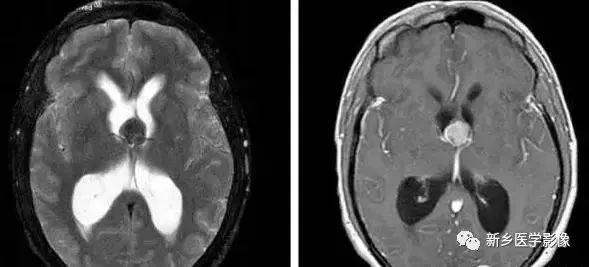

❹ Dandy-Walker’s综合症

又称第四脑室中侧孔先天性闭锁。在胚胎早期期,第四脑室正中孔及侧孔闭寒,导致四脑室呈囊性扩张,并伴有小脑蚓部及半球发育不良,扩张之四脑室向后发展,并与枕大池相连,使后颅窝扩大,小脑幕抬高。本病出现脑积水通常见于婴儿期,或者出生后即存在,但到成人期才发病。

❺ 四脑室内囊肿

四脑室囊肿可引起整个脑室系统梗阻扩大。

❻ 孤立性第四脑室

当导水管和第四脑室出口严重狭窄或完全阻塞时,四脑室则被孤立起来,这种情况称为孤立性第四脑室。